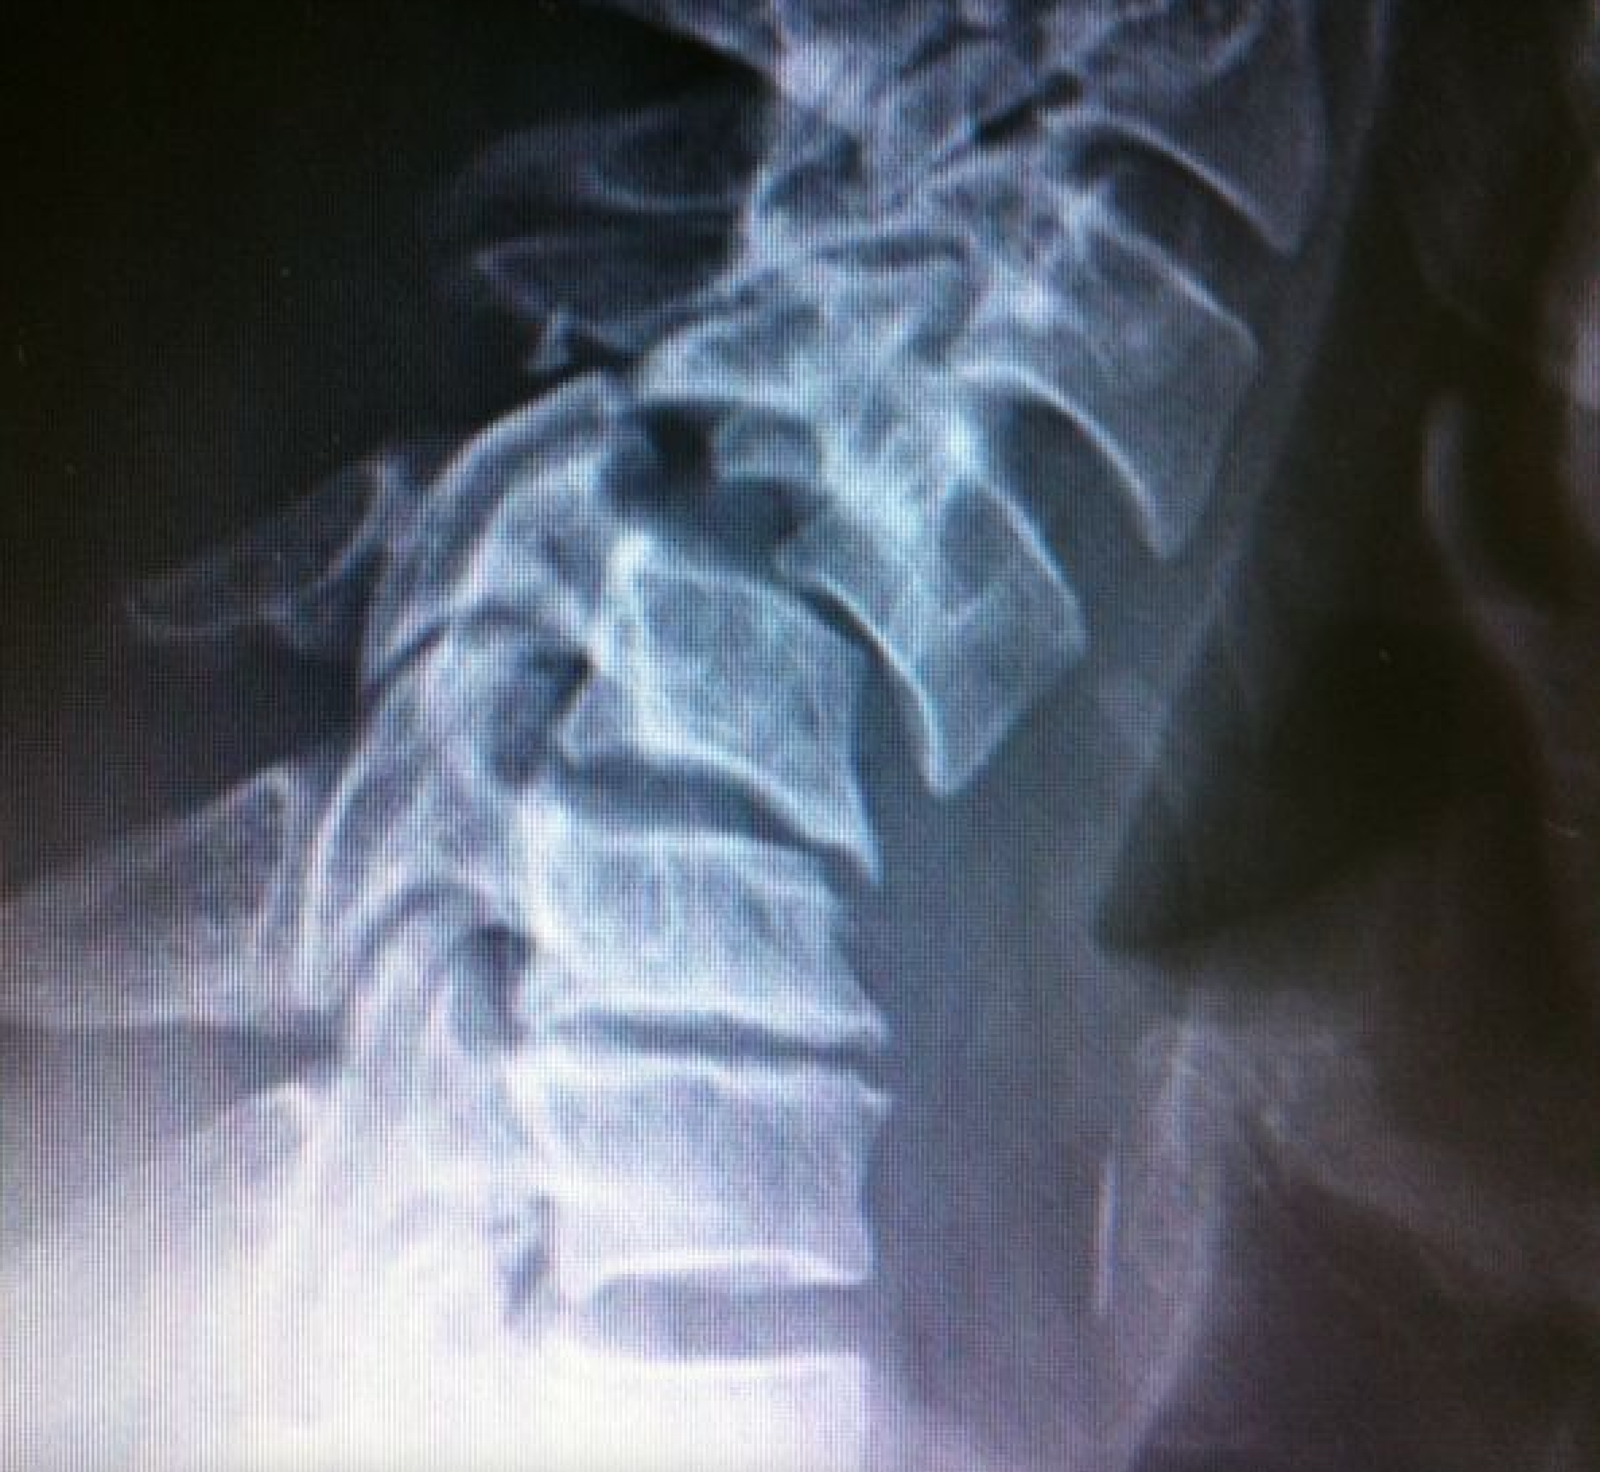

– La radiografía mostró una fractura-luxación de columna cervical traumática a nivel C4-C5.